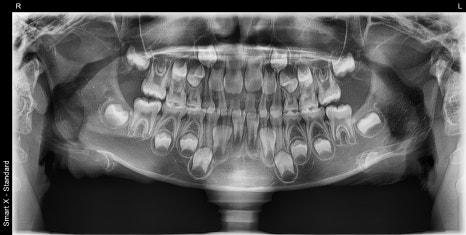

왼쪽 (파노라마 X-ray): 초진 시 외상으로 인해 치아나 턱뼈에 손상이 없는지 확인하기 위해 촬영한 파노라마 엑스레이입니다. 다행히 치아와 뼈에는 이상이 없는 것으로 확인되었습니다.